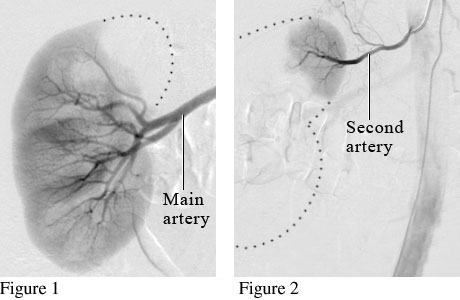

Angiogram of a Normal Kidney

Angiogram image of arterial supply to left kidney

Courtesy of Intermountain Medical Imaging, Boise, Idaho.

Many people have more than one artery for blood flow to the kidneys. Figure 1 is an angiogram showing the main artery supplying blood flow to the kidney. Figure 2 is an angiogram showing a second artery helping to supply blood to the kidney.